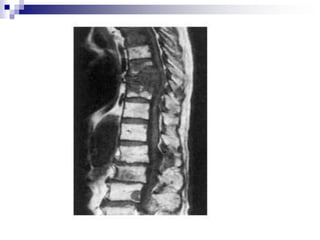

 X-ray

Standard radiographic series comprises AP,

lateral and open-mouth views.

All seven vertebrae should be visible in lat.

View.

Alignment of cervical lordotic curve.

Assess the disc spaces.

 MRI

No exposure to radiation

Provides excellent resolution of the disc and

neural structures

Most sensitive method of demonstrating

tumours and infection

Drawback: 20% of asymptomatic patients

show significant abnormalities, the scans

should be interpreted alongside the clinical

assessment.